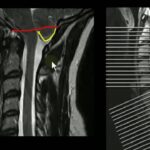

O treze tem vários tipos de fratura na coluna vertebral. Tem fratura luxação, fratura por efeito chicote, fratura por esmagamento. Então tem um monte de tipos de fraturas, tá? Geralmente, os chamados traumas raquimedulares são referentes a acidentes. Tá? Então, geralmente, a pessoa tem um acidente, uma coisa que ela não espera, e aí ela vai ser acidentada e pode ter uma lesão medular ou uma lesão da cauda equina. Então, só para vocês saberem, aqui isso aqui é na ordem que elas acontecem. Então, mergulho. Ele vai atrás aqui dos ferimentos por arma branca, mas basicamente acidente de carro é o que? Carro e moto, tá? Acidente de trânsito são os acidentes que geram mais lesões na coluna vertebral. Evidentemente, que gera um trauma raquimedular ou na coluna cervical. É um tipo. E na coluna lombar é outro. Então, em acidente de carro ele não escolhe onde vai ter problema. Pode ser a torácica ou a lombar. Esses termos aqui, ó, eles mudam um pouco. O famoso fafe, a gente chama de fafe. Mas isso aqui, antigamente, era chamado o ferimento por arma de fogo. Até bizarro assim, ó. Esse termo até vou explicar para vocês por que que mudou. Hoje em dia é chamado o ferimento por projétil de arma de fogo. Por que que mudou isso aí? Por que o ferimento por arma de fogo, a pessoa a gente entendia ser uma coisa só, dava por exemplo, e dava por exemplo numa cabeça da pessoa. É um ferimento na cabeça por uma arma de fogo, não foi pelo tiro. Então isso aqui é um fafe. Fica com cara de uma coronhada. Hoje em dia, você tem que explicar tudo né, senão pessoal da alta, tá errado esse termo. Então, tudo o que for mais ajustado, o tiro própria mãe, e ele é chamado ferimento por arma branca. Aí é que entra também os ferimentos corto-contusos, tá? Que são ferimentos a faca e outros elementos como uma chave de fenda, martelo, esse tipo de coisa. Então, aqui é uma arma branca qualquer. Tudo que não é arma de fogo é arma branca. Espeto de churrasco também. Quedas, então quedas que a pessoa não prevê podem causar uma lesão. Então, a pessoa cai da laje, tomou um choque na laje e caiu. Tem vários tipos de lesões. E os esportes, aí não precisa nem ser esporte radical, tá? Esportes em geral. Geralmente, com algum tipo de contato, podem gerar lesões por traumatismos. Oi educarte então assim, é importante que vocês entendam que dependendo da parte da coluna afetada, o mecanismo de lesão é diferente. Então assim, quando fala trauma fechado, é quando você não tem corte, não tem fratura exposta, nada do tipo. Tá bom, então, é quando você tem uma combinação de forças que geram a explosão, rupturas ligamentares, outras agem excessivas dos corpos vertebrais ou dos discos intervertebrais. Depende de onde vai ser a lesão. Então, o que a gente tem? Várias forças agindo. Forças de contusão, compressão ou tração. Interfagem forças de contusão, você vai ter uma pancada direta no local. Tá? Então, quando a gente tem um trauma contuso, é um trauma onde você tem uma forte energia. O que que acontece quando a pessoa toma um tiro? Qual que é aquele tipo de ferimento que ela tem? Contusão, compressão, tração ou queimadura? Quem que vocês acham que é aquele ferimento? É só para vocês terem uma ideia. Tiro é um ferimento contuso de alta energia. O que é contuso? É quando você dá uma pancada forte. Então, quando a pessoa toma um tiro, quando tiro à queima-roupa ela, evidentemente, só que depois que a bala sai, é só o projétil. Então, quando ele bate no corpo, ele perfura e gera uma contusão. Tá bom, então essa contusão que gera lesão tecidual. Tá? Então, as lesões na coluna que a gente vai ver então por contusão, quando a pessoa toma um tiro, os locais mais comuns de lesão são traumas raquimedulares segmento cervical baixo, segmento torácico baixo e segmento lombar alto. Tá? Então, segmentos toracolombares e cervical baixo são os segmentos cervicais mais baixos. Quando a pessoa pula, por exemplo, uma pessoa tenta se matar de uma ponte e pula e cai em pé, o que que acontece? A gente tem um trauma de alta energia nos pés. É uma coisa interessante que eu dificilmente vocês vão ver uma pessoa com uma fratura de calcâneo mesmo caindo de uma altura grande. Porque o calcâneo é um osso que é composto basicamente de uma parte por outro esponjoso. Então, ele absorve e dissipa muito impacto. Tá? Então, ele acaba, na hora que você fica sobre os pés, se o cara caiu para o lado, ele não fratura o calcâneo. Tá bom? Que que ele fratura? Fratura tíbia, fratura fêmur, fratura coluna vertebral. Então, são fraturas por dissipação de energia sobre o esqueleto. Eu já vi bastante traumas desse tipo lá no hospital. Você fala: “mais às vezes são mais altas”. Torácicas puras são menos frequentes.